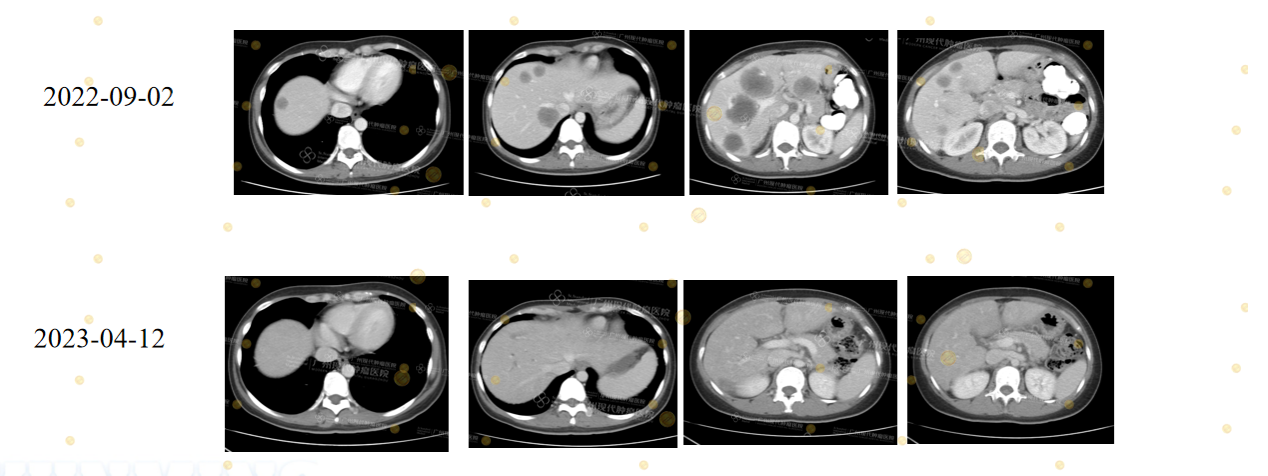

3.3 về hiệu quả điều trị đột phá cho bệnh nhân ung thư đại trực tràng di căn gan (CRLM) có trạng thái MSS. Giới y khoa trước đây thường tin rằng bệnh nhân MSS rất khó đáp ứng với các phương pháp điều trị mới. Đây là một rào cản lớn trong quá trình thực hành lâm sàng. Tuy nhiên, các hồ sơ bệnh án tại Bệnh viện ung bướu St.Stamford Quảng Châu đã mang đến một góc nhìn khác. Chúng tôi nhận thấy việc kết hợp liệu pháp sinh học, thuốc nhắm trúng đích và các phương pháp điều trị tại chỗ mang lại kết quả rất khả quan. Khối u của một số bệnh nhân đã thu nhỏ đi một cách rõ rệt. Vài trường hợp thậm chí đã đạt đến mức gần như thuyên giảm hoàn toàn. Những quan sát thực tế này cung cấp những bằng chứng y khoa vô giá cho các nghiên cứu về MSS trong tương lai.

(Chú thích: Bệnh nhân nam 30 tuổi ung thư trực tràng sau phẫu thuật bị di căn gan đa ổ (MSS/pMMR, NRAS G12D). Sau khi áp dụng điều trị sinh học đa tuyến kết hợp liệu pháp nhắm trúng đích và điều trị tại chỗ (Sintilimab + HAIC + Bevacizumab + MWA), các khối u di căn gan đã tiến gần đến mức đáp ứng hoàn toàn (CR) hoặc không còn dấu hiệu bệnh (NED). Trường hợp này cho thấy những bệnh nhân CRLM nhóm MSS vẫn có thể đạt được hiệu quả điều trị mang tính đột phá.)